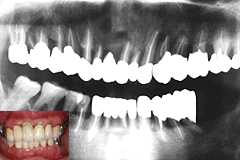

| 54歳 男性 | 術後3年 |

| 初診時 パノラマ | 動揺もなく100%機能発揮、経過良好。 |

口腔内およびX線所見:

口腔内全体に縁下歯石の沈着が著しく、ほとんどの歯が動揺度4。清掃状態も不良で、排膿・

口臭が著明。X線的にも歯槽骨の破壊が著しく、常識ではほとんどの歯が保存不可能と思われる。

しかし、下顎に入れた義歯に対しての不満から残存歯牙の保存を強く希望。治療と

メインテナンスに深い理解を示していることもあり、可及的に歯牙を保存することとした。

処置および経過:

初期治療終了後、全顎の抜髄と歯周外科処置をおこなった、尚、手術に際して

Nd:YAGレーザー照射による根面処理を併用した。

全顎の補綴処置終了後、1か月毎のメインテナンスに移行。7」にしばしば腫脹が認められる

ものの残存歯は動揺は一切なく咀嚼機能を果たしており、臨床上経過良好。

考察:

X線的には、歯槽骨の回復した所と破壊された所とが混在しており一概に良好とはいえないが、

7」を除き歯肉腫脹もなく順調に経過している。「何でも咬めます。」と言う本人の笑顔は、

何よりである。